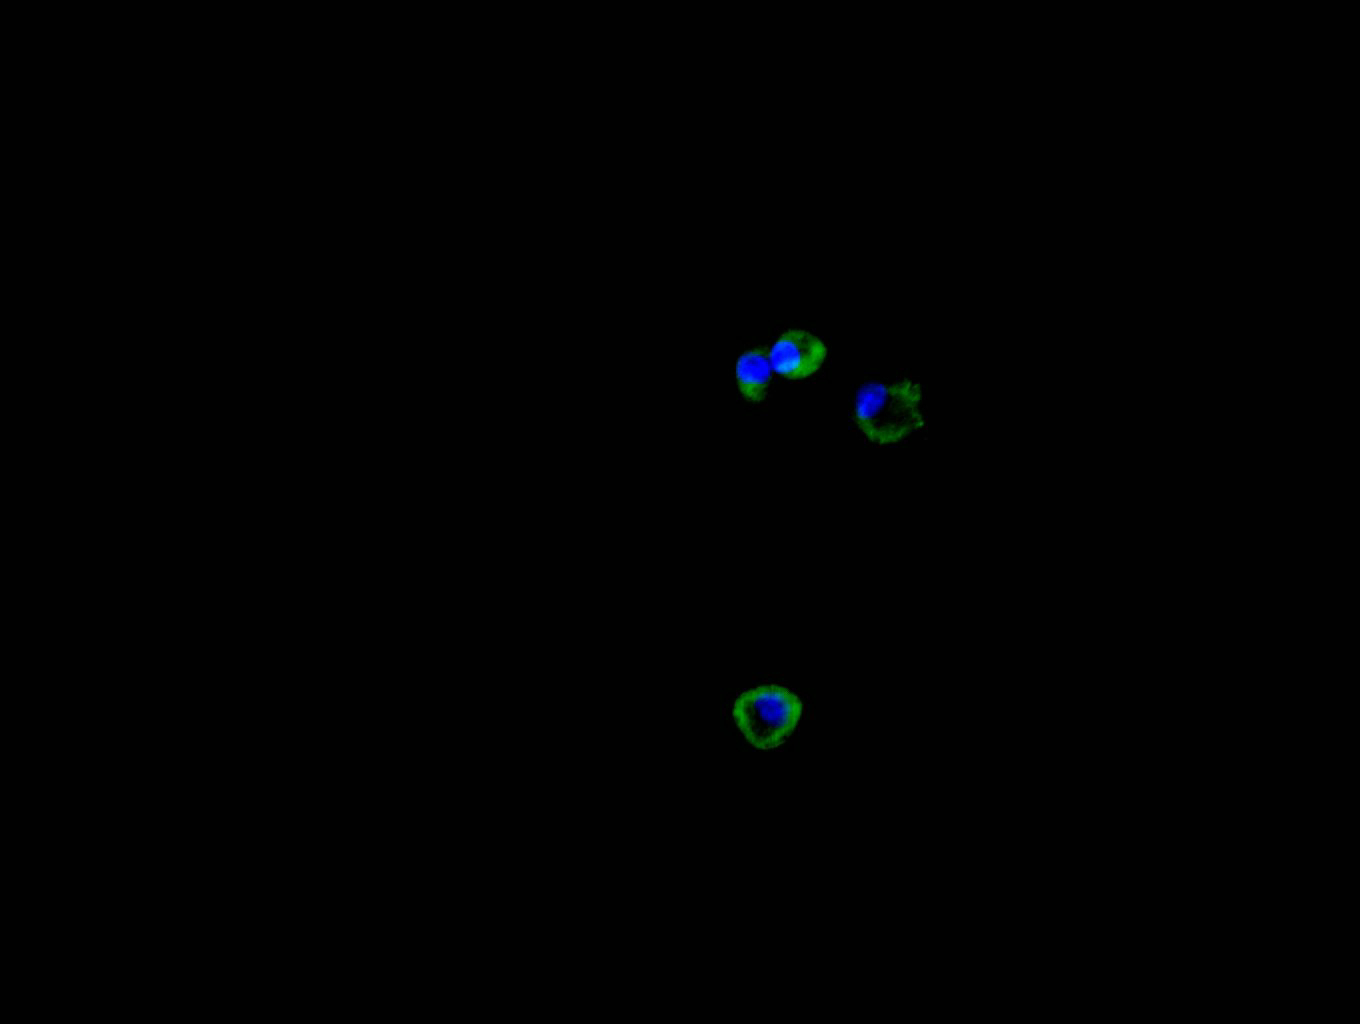

Immunofluorescence staining of HEPG2 cell with CSB-RA006163MA1HU at 1:30, counter-stained with DAPI. The cells were fixed in 4% formaldehyde and blocked in 10% normal Goat Serum. The cells were then incubated with the antibody overnight at 4C. The secondary antibody was FITC-conjugated AffiniPure Goat Anti-Mouse IgG(H+L).